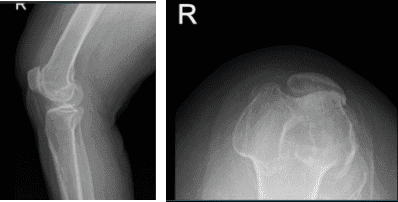

Aparte de esto, receté Relafen como antiinflamatorio. Los resultados de las radiografías y resonancias magnéticas se presentaron en la consulta. Los resultados de las radiografías mostraron cambios degenerativos osteoartríticos moderados y leves.

Resonancia magnética de la rodilla derecha

Impresión del resultado de la resonancia magnética es la siguiente: edema de médula ósea en la parte periférica anterior de la meseta tibial medial con ligera aplanamiento e irregularidad de la superficie articular; hay una impactación subcondral de bajo grado o fractura por estrés en cicatrización.

Desgarro complejo del cuerno posterior del menisco medial, incluyendo un colgajo meniscal desplazado que adentra en la raíz posterior y mide 1 cm de longitud. Artrosis patelofemoral severa. Artrosis femorotibial moderada. Derrame articular moderado.